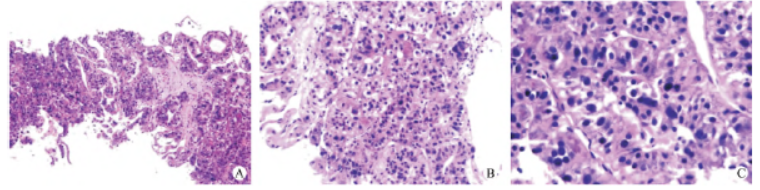

患者经过院内多学科会诊后,给予碳离子治疗,靶区勾画标准:患者取仰卧位于定位板上,真空垫及热塑膜固定,体表画标记线,CT 扫描层厚为3 mm,扫描范围自气管分叉至腰5 椎体,扫描后的CT 图像传至“大图”计划系统进行靶区勾画,GTV 勾画为核磁上可见的肝脏病灶;CTV 根据4DCT在GTV 基础上外扩0.5 cm,头脚方向1.2 cm;PTV 在CTV 的基础上外扩0.3 cm,在脊髓、肋骨、食管、胃、结肠等处个体化裁剪,分为PTV1、PTV2、PTV3、PTV4。

要求处方剂量为PTV1 /PTV2 /PTV3 /PTV4:66 Gy(RBE)/10 f,95% 的PTV 满足处方剂量,点扫描。危及器官剂量限量,每周五次,碳离子的剂量以光子当剂量(GyE)表示,其定义为物理剂量乘以碳离子的RBE(图3)。

图3 靶区勾画A - D:CIRT 计划使用碳离子计划[ciPlan,1.0 版,中国兰州近代物理研究所(IMP)]进行,包括生物计划优化。治疗计划包括使用碳离子治疗计划(ciTreat,1.0 版,IMP)治疗计划软件系统的生物治疗计划优化程序。